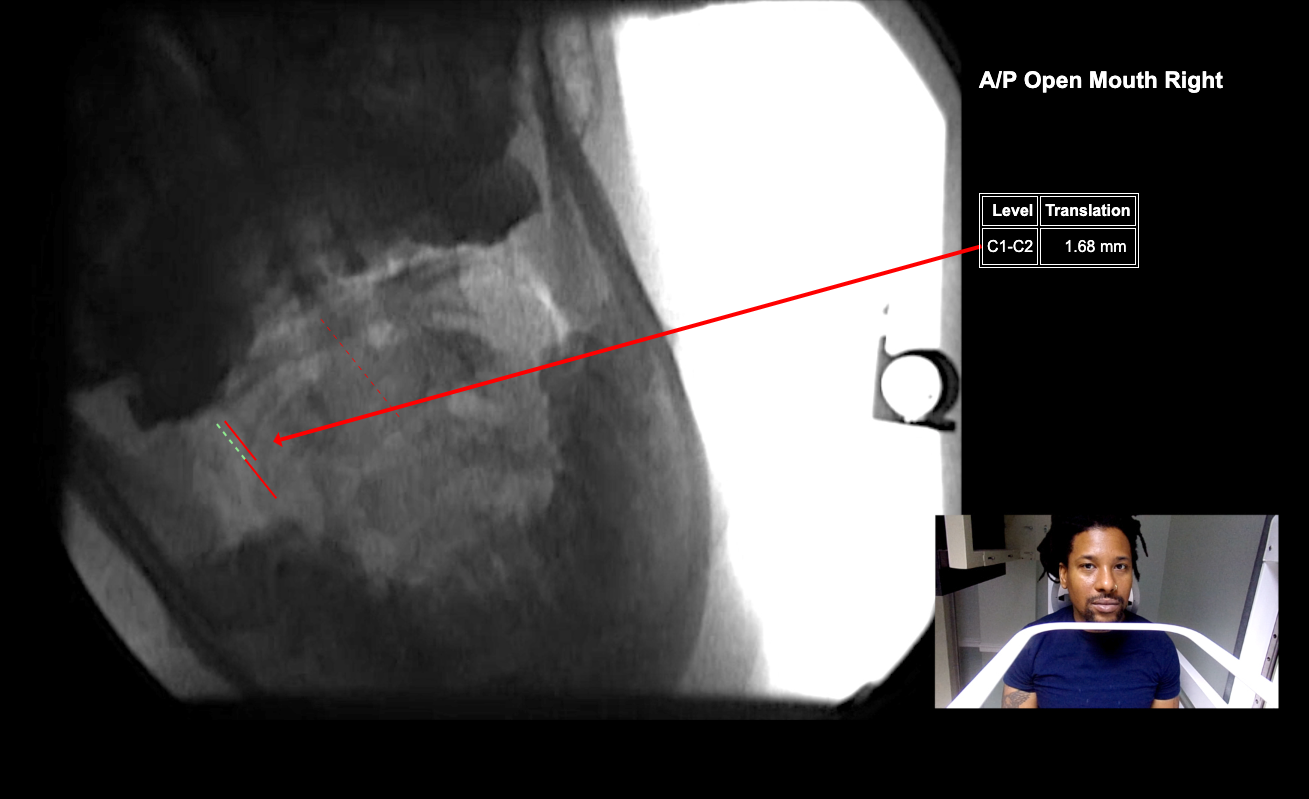

Image Name Image Type Image